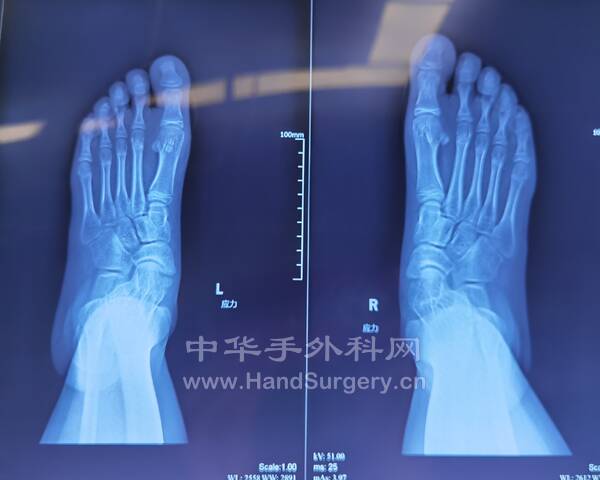

今日得偿所愿,上午跟着老师参观双侧青少年柔韧性扁平足微创扁平足制动器矫正术,双侧副舟骨切除胫后肌腱止点重建术的

13岁男性患者,用的威高扁平足制动器(但大博2代扁平足制动器相对较好)。

副舟骨切除,用直径3.0mm可吸收螺钉固定,与胫后肌腱加固缝合,腱骨缝合,用2.5mm克氏针在舟骨上打孔,放入强生直径3.0mm可吸收铆钉(丝线亦为50%可吸收线),远端与胫后肌腱编织缝合加固!术后6周不能行走。